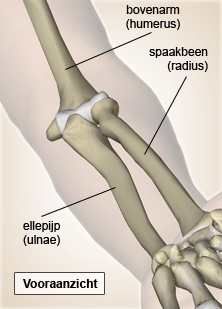

Elleboog